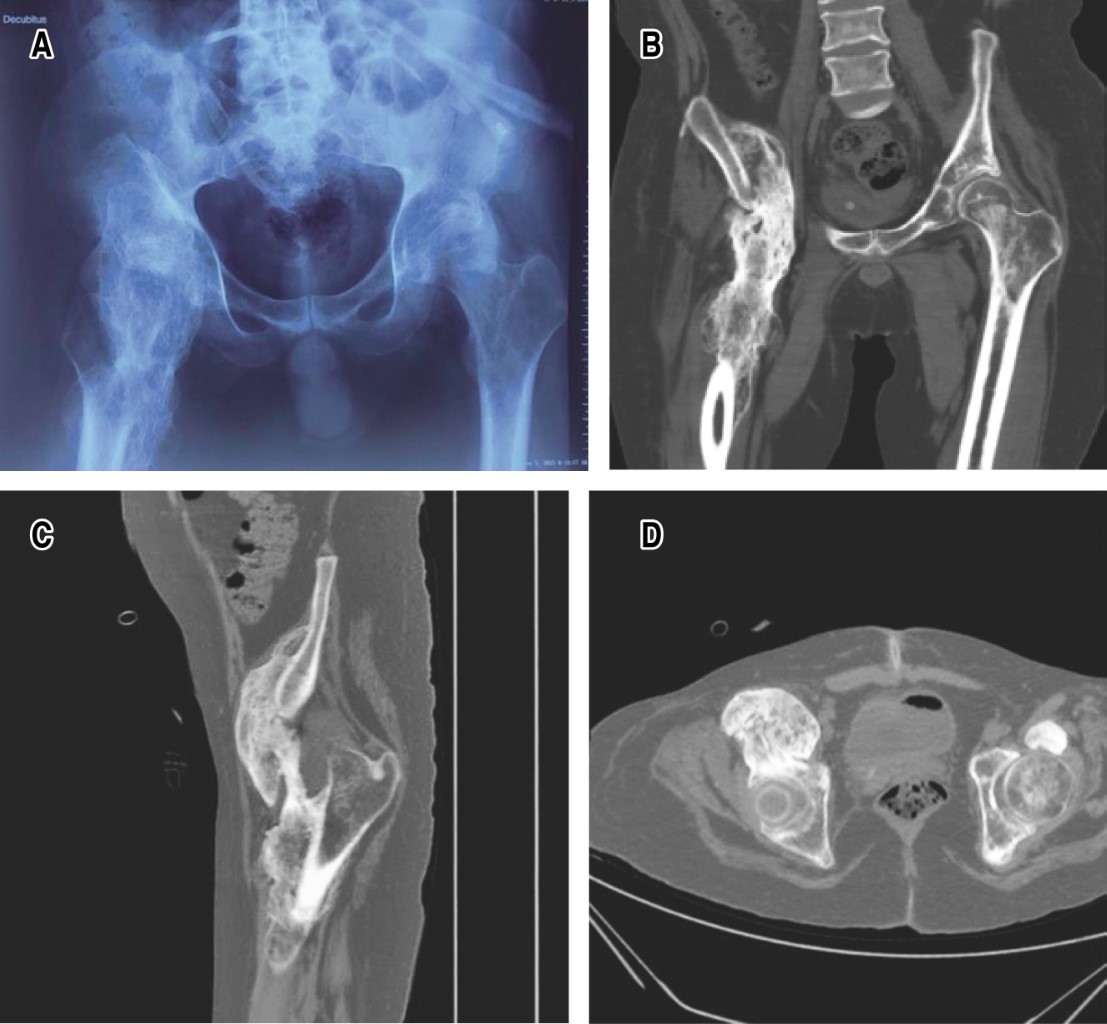

El paciente fue revisado transcurridas dos y seis semanas, tres y seis meses. La herida cicatrizó sin ninguna complicación, y los rangos de movilidad se han mantenido durante el seguimiento a seis meses. Se realizó una radiografía anteroposterior. Los controles radiográficos se consideraron adecuados y sin observarse complicaciones (fracturas, datos radiográficos de nueva formación ósea) (Figura 2).

Figura 2